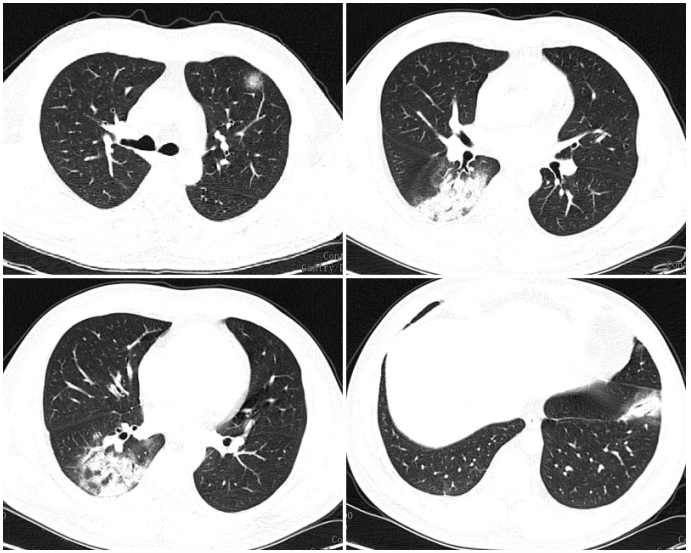

求助68岁男性突发重症肺炎到底是什么感染细菌病毒支原体

图片尺寸3120x4160